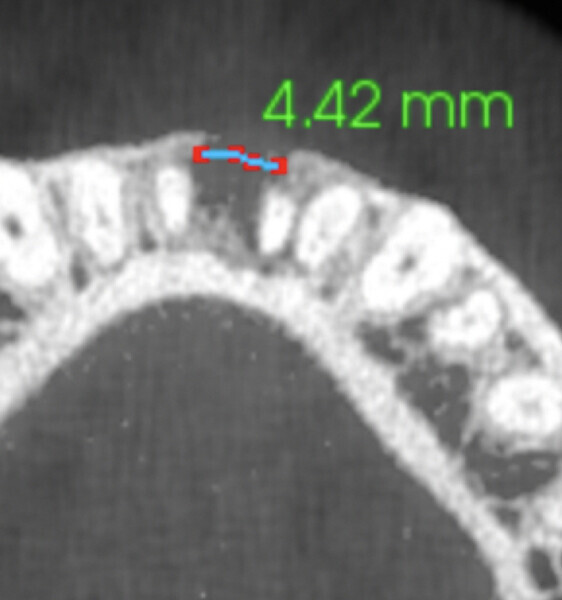

A radiograph was taken of the immediate postoperative situation and at the nine-month follow-up. Comparison showed bone apposition between the two central incisors (Fig. 4). An i-CAT scan was also taken at the nine-month follow-up to check the bone growth. The horizontal view, taken at the same level as that taken preoperatively, clearly showed the reduction of the gap from 14.11 mm to 4.42 mm at the cortical level and the trabecular bone showed the same trend in healing (Fig. 5). The vertical view showed that the bone on the buccal plate was growing towards the root and growing vertically (Fig. 6). Almost 8.2 mm in height had been regained and in direct contact with the roots of the teeth. Indeed, when provided with a scaffold on which to grow, the bone can grow in all directions, including vertically, where there was an open periodontal pocket. This is the major breakthrough of this technique. No bone grafting material or a membrane was placed. The periosteum was in great condition, and for me, it was the best membrane I could wish for.

Fig. 6a: Horizontal view of the i-CAT scan taken at the nine-month follow-up showing a bone defect of only 4.42 mm.